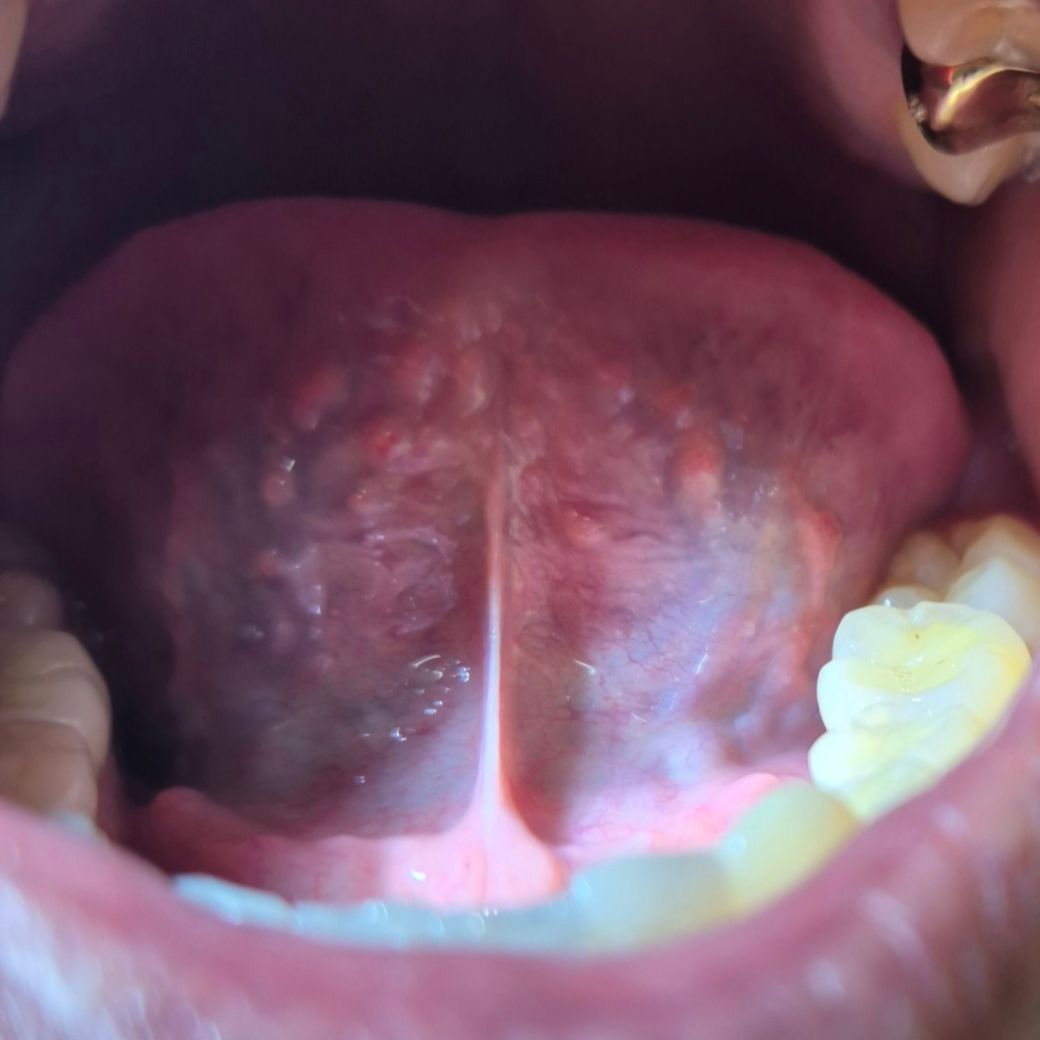

의사 선생님들 혀바닥 밑에 돌기(여드름) 있는데 괜찬은 건가요??

의사 선생님들 혀바닥 밑에 돌기(여드름) 있는데 괜찬은 건가요?? 작년 부터 알았는데 다 있는 줄 알았어요..

크게 신경 안썻는데 혹시 괜찬은건가요?? 통증 x ,

말씀하신 부분은 정상 해부학적 구조물로 걱정하지 않으셔도 됩니다. 채상주름(Fimbriated fold)라고 부르는 구조물로 사람마다 없는 사람조 있고 질문자님보다 훨씬 길고 뾰족하게 튀어나와있는 분들도 있습니다. 간혹 컨디션에 따라 조금 저 커지기도, 작아지기도 하지만 정상적인 구조물이니 너무 걱정하지마시고 그대로 두셔도 됩니다.

혀 하방에는 침샘, 림프조직, 혈관 등 다양한 해부학적 구조가 있어 정상 상태에서도 울룩불룩합니다